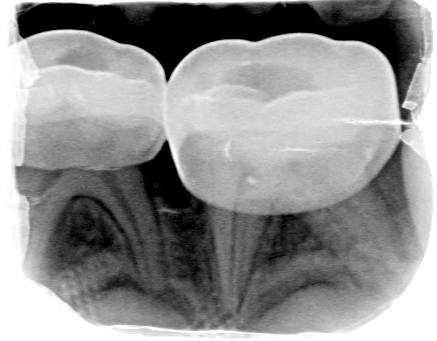

Afbeelding 3a: Röntgenfoto's op de leeftijd van 6 jaar, juli 2018.

Afbeelding 3b: Röntgenfoto's op de leeftijd van 6 jaar, juli 2018.

Afbeelding 3c: Röntgenfoto's op de leeftijd van 6 jaar, juli 2018.

Afbeelding 3d: Röntgenfoto's op de leeftijd van 6 jaar, juli 2018.

Jenny is 6 jaar. Er worden röntgenopnames en kleurenfoto’s gemaakt (Afb. 3 en 4). Op de röntgenfoto’s lijken de bovenmolaren ernstig aangetast, maar ze zijn hard en inactief. De niet-gerestaureerde bovenmolaren en kronen met gerestaureerde ondermolaren zijn vrij van ontsteking. Jenny kwam voor mondonderzoek om de 4-6 mnd.

Voor het maken van röntgenfoto’s werd een doormidden geknipt maat 0 fosforplaatje gebruikt. Maat 0 is voor veel jonge kinderen te groot en moeilijk te accepteren.